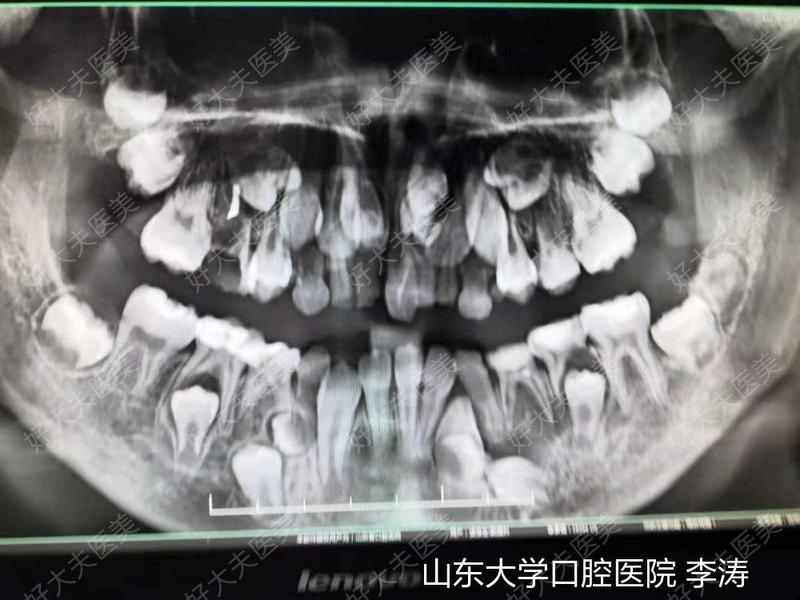

治療前患兒九歲,上前牙未萌,拍牙片發(fā)現(xiàn)前牙區(qū)兩顆多生牙及一顆門(mén)牙倒著生長(zhǎng)。同時(shí)發(fā)現(xiàn)左側(cè)下頜區(qū)域存在牙瘤,由于患者年齡較小,不能配合手術(shù),遂全麻下行埋伏牙多生牙及牙瘤摘除術(shù),術(shù)后于正畸科就診進(jìn)行后續(xù)治療。若發(fā)現(xiàn)兒童牙齒未萌或門(mén)牙之間間隙過(guò)大情況,建議及時(shí)就醫(yī)行拍片檢查,以免延誤治療時(shí)機(jī)!治療后治療后0天術(shù)后重新拍片見(jiàn)埋伏牙完全拔除,牙瘤無(wú)殘留。

治療前患兒替牙列期,8顆多生埋伏牙,形態(tài)各異,經(jīng)兒童牙病科會(huì)診需要拔除其中6顆(考慮另外兩顆拔除時(shí)可能損傷恒牙胚),同時(shí)要求拔除滯留乳牙。我們術(shù)前通過(guò)CBCT對(duì)每一個(gè)牙進(jìn)行三維重加,并用不同的顏色進(jìn)行標(biāo)注(黑色標(biāo)記為待拔除多生牙)。從而保證了手術(shù)中的精準(zhǔn)合快速。治療后治療后3天患兒替牙列期,8顆多生埋伏牙,形態(tài)各異,經(jīng)兒童牙病科會(huì)診需要拔除其中6顆(考慮另外兩顆拔除時(shí)可能損傷恒牙胚),同時(shí)要求拔除滯留乳牙。我們術(shù)前通過(guò)CBCT對(duì)每一個(gè)牙進(jìn)行三維重加,并用不同的顏色進(jìn)行標(biāo)注(黑色標(biāo)記為待拔除多生牙)。從而保證了手術(shù)中的精準(zhǔn)合快速。